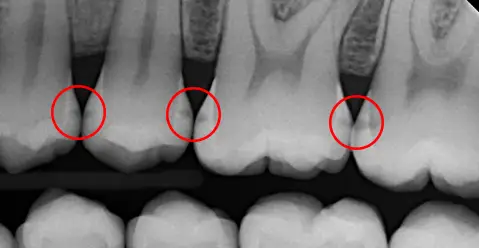

2. No digital radiographs (x-rays)

Having access to radiographs (x-rays) is very important in diagnosing early decay. Back in the day, you couldn’t take a digital radiograph and work out exactly what was happening inside the tooth then and there in the dental surgery. Instead, the x-ray film had to be sent away to be developed – similar to old photos. This meant that on the day, dentists had to rely more on what they could see in the mouth and the patient’s symptoms.